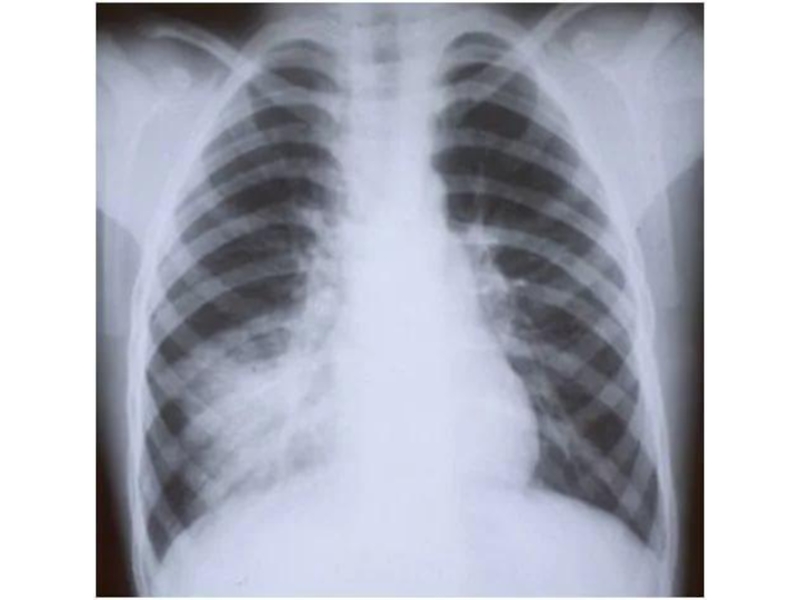

Слайд 60Очаговая бронхопневмония (уплотнение легочного рисунка в прикорневой зоне в нижней доле

правого легкого)